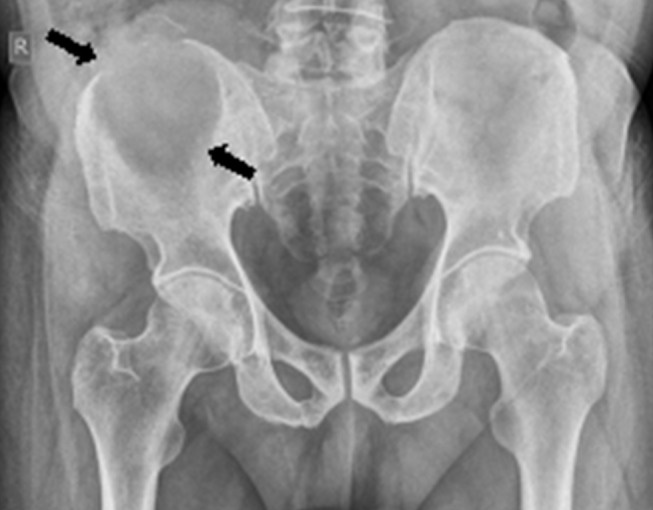

Imagen (enfoque 2026: precisión y correlación)

Radiografía/TC

Hallazgos típicos:

- Lesión lítica, a menudo excéntrica, metafisaria

- Borde esclerótico variable

- Septaciones internas (“lobulada”)

- Expansión con adelgazamiento cortical; calcificación suele ser ausente o mínima